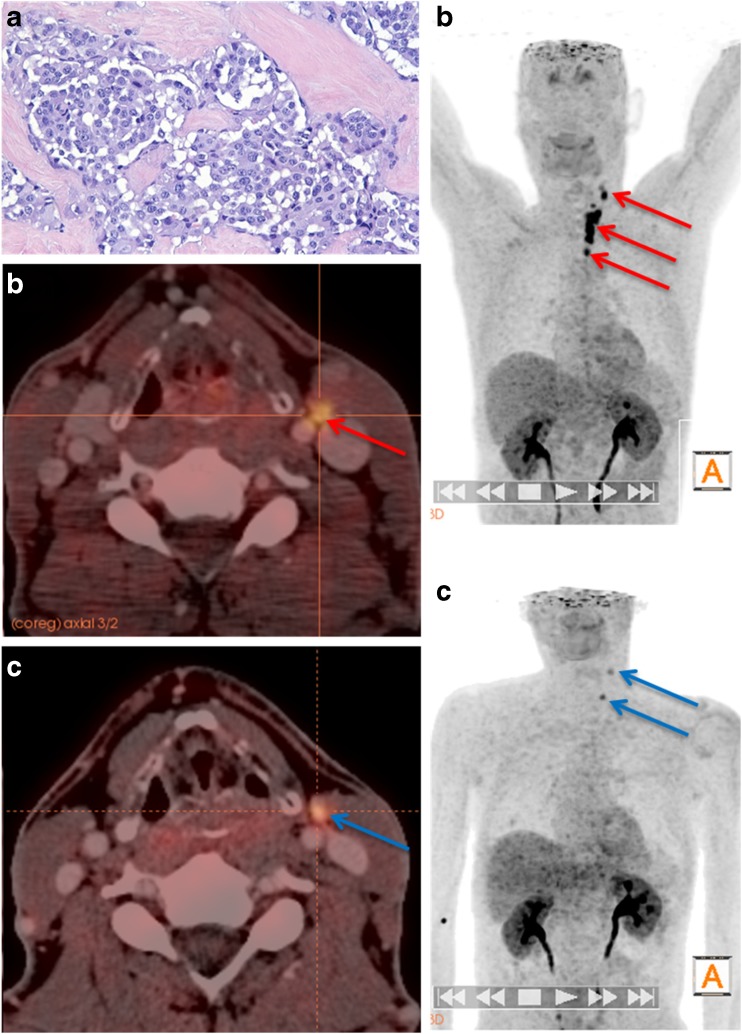

Fig. 3.

A 53-year-old male patient with a histologically proven medullary thyroid carcinoma (MTC) after thyroidectomy. a Histology shows MTC with desmoplastic stroma reaction (H&E, ×400). b Preoperative [18F]DOPA PET/CT shows focally increased [18F]DOPA uptake in the left thyroid lobe and in multiple lymph nodes of the central and lateral neck (N1a+b). c [18F]DOPA PET/CT in the same patient after total thyroidectomy and lymph node dissection with persistently elevated basal calcitonin levels still shows increased [18F]DOPA uptake in residual level IIa and level IV lymph nodes on the left

Two months after surgery, 14 patients showed measurable bCtn levels and were categorized as having persistent MTC, while 17 patients showed no detectable levels of bCtn and sCtn. The median (range) postoperative bCtn, sCtn and CEA levels were 0.5 pg/ml (0–23,647 pg/ml), 0.5 pg/ml (0–244,000 pg/ml) and 2.6 μg/ml (0–1,426 μg/ml), respectively. LN with increased DOPA decarboxylase activity were detected on follow-up [18F]DOPA PET/CT examinations in these patients ([18F]DOPA PET/CT imaging in representative patients is shown in Figs. 3, 4, 5, and 6). The patient with the highest Ctn levels showed liver metastases on the first follow-up scan 2 months after surgery.